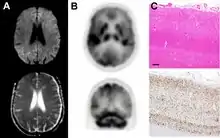

MRI of iCJD because of growth hormone

The defective protein can be transmitted by contaminated harvested human brain products, corneal grafts,[23] dural grafts,[24] or electrode[25] implants and human growth hormone.[26]

Imaging of the brain may be performed during medical evaluation, both to rule out other causes and to obtain supportive evidence for diagnosis. Imaging findings are variable in their appearance, and also variable in sensitivity and specificity.[43] While imaging plays a lesser role in diagnosis of CJD,[44] characteristic findings on brain MRI in some cases may precede onset of clinical manifestations.[45]

Brain MRI is the most useful imaging modality for changes related to CJD. Of the MRI sequences, diffuse-weighted imaging sequences are most sensitive.[46] Characteristic findings are as follows:

dwMRI, FDG PET and post mortem histology from a patient who presented with sCJD aged 66

Brain FDG PET-CT tends to be markedly abnormal, and is increasingly used in the investigation of dementias.

• Patients with CJD will normally have hypometabolism on FDG PET.[50]